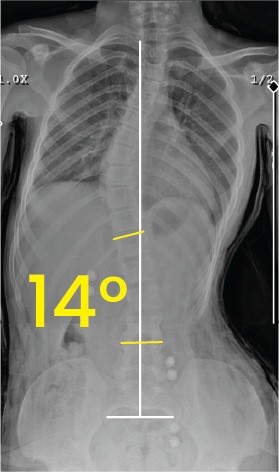

Toraks röntgen görüntüsünde 30 derecelik skolyoz eğriliği sarı açılarla ve beyaz çizgilerle işaretlenmiş.Göğüs ve bel bölgesini gösteren röntgen, omurga eğriliğinin 14 derece olduğunu belirtir.

Toraks bölgesinde 34 derece eğri omurga ve cerrahi implantların olduğu röntgen görüntüsü.X-ray image of a human torso showing the spine with surgical implants and a 14-degree curvature marked.